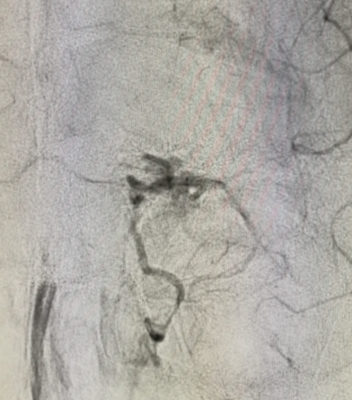

Un eccezionale intervento di Neuroradiologia interventistica neurovascolare all’encefalo è stato effettuato all’Ospedale Cannizzaro di Catania su un bambino di 10 anni proveniente da Ragusa, affetto da una rara MAV (malformazione artero-venosa), che per la sede e la natura, se non diagnosticata e trattata, non gli avrebbe lasciato speranza di vita. Il bimbo, infatti, nelle scorse settimane aveva accusato una forte cefalea, trattata inizialmente con antinfiammatori. Data la persistenza del disturbo, dopo visita pediatrica, era stato ricoverato all’ospedale di Ragusa, dove la prima risonanza aveva evidenziato un focolaio emorragico. Quindi, l’invio all’Ospedale Cannizzaro per il trattamento specialistico. Data l’età del paziente e la sede relativamente atipica dell’emorragia, il piccolo è stato sottoposto a risonanza magnetica che ha messo in evidenza una micro-MAV: un groviglio venoso nella “arteria ricorrente di Heubner”.

“Una MAV su questa arteria è rarissima e documentata da pochi casi in letteratura – spiega il prof. Concetto Cristaudo, direttore della Neuroradiologia dell’Azienda Cannizzaro e a capo dell’équipe che ha operato –. Il paziente era stato colpito da una emorragia nucleare antero basale e frontale posteriore sinistra, condizioni abbastanza gravi non tanto per la clinica silente quanto per la possibilità di un nuovo sanguinamento che avrebbe certamente portato alla morte. Di qui la difficoltà di riuscire a navigare strumentalmente questa arteria”.

L’intervento, deciso dopo confronto con i neurochirurghi, è riuscito perfettamente. Grazie alla collaborazione del team di anestesisti, coordinato dalla dott.ssa Maria Concetta Monea, il bambino è stato sottoposto ad angiografia solo sedato con maschera laringea, e non intubato. Fondamentale anche la tempistica: i neuroradiologi interventisti, incrociati i dati con quelli della settimana precedente, hanno atteso il tempo minimo necessario che si detendesse l’emorragia e nello stesso tempo che si avesse certezza di intervenire sulla parte malata. “Si è trattato di un intervento ad elevatissimo rischio e complessità – aggiunge Cristaudo – con altissimo rischio di morte dovuto al materiale usato per il trattamento tramite catetere. Il bambino è stato embolizzato efficacemente, si è svegliato in giornata e il giorno successivo è stato ricoverato in Neurochirurgia”. Ora gioca con i suoi videogiochi, mamma e papà accanto, e a breve potrà essere dimesso.